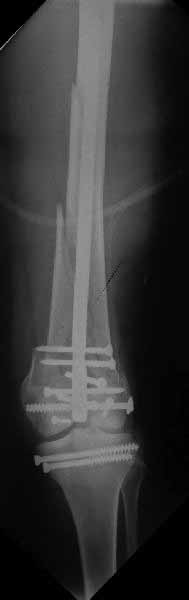

Ответ на эту часть Вашего поста – вложенный файл. Больная оперирована неделю назад по поводу открытого перелома дистального эпиметафиза бедренной кости. После операции она идёт в рентгенкабинет для выполнения послеоперационной контрольной рентгенографии, представленной на слайдах 10 и 11. Узнав, почему её фотографируют, просила передать Вам, Антон, привет.

В приложении пример недавней операции, C3, открытая репозиция, фиксация мыщелков спицами и винтами, ретроградный синтез большеберцовым гвоздем 10,5 мм диаметром, винты 5 мм.